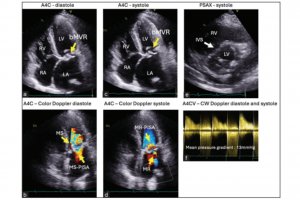

Cautionary Tale of Failed Mitral Valve Replacements

This case report discusses the tragic outcome of a young female patient in her early 50s with rheumatic heart disease (RHD) who underwent multiple mitral valve replacements. Initially diagnosed with…